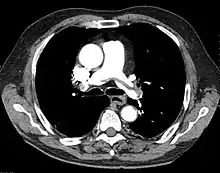

"Saddle" embolism on CT. The filling defect in the pulmonary artery is the clot.

A pulmonary embolism (PE) is an obstruction of the pulmonary arteries.[13] Deaths from PE have been estimated at ~100,000 per year in the United States. However, this may be higher in recent years.[16] Most often, the obstruction is a blood clot that traveled from elsewhere in the body. Most commonly, this is from a deep vein thrombosis (DVT) in the legs or pelvis.[13] Risk factors are conditions that increase the risk of clotting. This includes genetic (factor V Leiden) and acquired conditions (cancer).[17] Trauma, surgery, and prolonged bed-rest are common risks. Covid-19 is a recent risk factor.[18]

A chest X-ray can rapidly identify a pneumothorax, seen as absence of lung markings. Ultrasound can show the lack of lung sliding. However, imaging should not delay treatment.[8] CT angiography is the standard of diagnosis of pulmonary embolism. Clots appear in the vasculature as filling defects.[18]